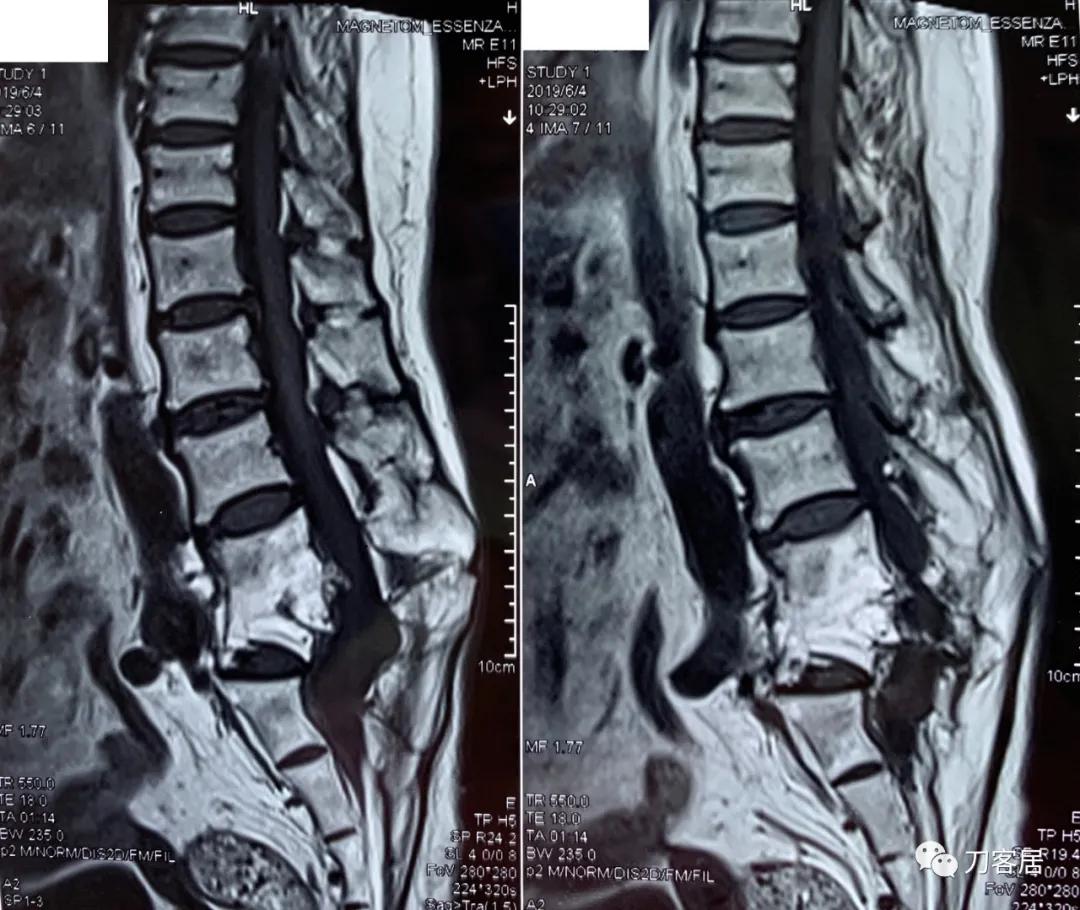

家属携带的影像学检查提示腰4-骶1病灶清除植骨融合术后改变,骨质疏松严重,未见椎旁脓肿以及结核病灶复发破坏。血沉、C反应蛋白化验检查结果正常。

诊断:腰4-骶1病灶清除植骨融合术后,严重骨质疏松症。

图5. 20190604腰椎MRI02

图6. 20190604腰椎MRI01

图7. 20190604腰椎MRI03

图8. 20190604腰椎MRI04